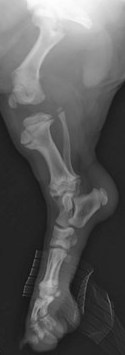

Y para muestra, un botón. En esta tabla te ponemos los tiempos de cierre de las placas de crecimiento de un cachorro:

| HUESO | CIERRE PLACA DE CRECIMIENTO |

|---|---|

| Húmero (a la altura de la escápula) | 10-12 meses |

| Radio (a la altura del codo) | 9-11 meses |

| Huesos de los dedos | 6-7 meses |

| Huesos de la pelvis | 5-6 meses |

| Fémur (a la altura de la cadera) | 9-11 meses |

| Tibia (a la altura de la rodilla) | 10-14 meses |

Y aquí te ilustramos de lo que estamos hablando con varias radiografías de cachorros en las que puedes ver perfectamente que los huesos parecen «flotar» en el espacio: